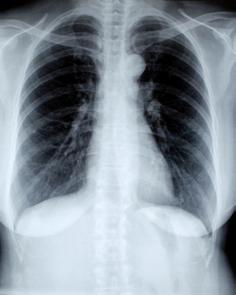

Rekordowa terapia ECMO u pacjenta z Covid-19

W listopadzie 2020 roku 59-letni mężczyzna – lekarz, zakażony koronawirusem SARS-CoV-2, trafił do szpitala. Spędził tam 122 dni, z czego aż 68 dni był wspomagany systemem ECMO. To rekordowo długa – w skali kraju i świata – terapia. W porównaniu, „standardowa” terapia ECMO trwa ok. 20 dni. Za sukcesem stoją medycy z Górnośląskiego Centrum Medycznego im. prof. Leszka Gieca Śląskiego Uniwersytetu Medycznego w Katowicach.

Pacjent trafił na Oddział Pneumonologii szpitala w katowickiej dzielnicy Ochojec. Pomimo wdrożonego leczenia jego stan dramatycznie się pogarszał. Ze względu na stopień uszkodzenia płuc podjęto decyzję o przekazaniu go do Oddziału Anestezjologii i Intensywnej Terapii z Nadzorem Kardiologicznym i podłączeniu do urządzenia, które zastąpiło funkcję uszkodzonych płuc, czyli do aparatu do pozaustrojowego utlenowania krwi - VV ECMO. W ten sposób był wspomagany aż 68 dni. Rekordowo długa terapia pozwoliła mu na samodzielne, wydolne oddychanie i powrót do codziennej praktyki lekarza rodzinnego.

ECMO jest alternatywnym leczeniem pacjentów, u których do wyleczenia nie wystarcza już respirator. ECMO stosuje się w najbardziej wyspecjalizowanych oddziałach, ponieważ jest to skomplikowana procedura, wymagająca perfekcyjnego nadzoru. Wyleczenie pacjenta było możliwe dzięki współpracy lekarzy kilkunastu specjalności.